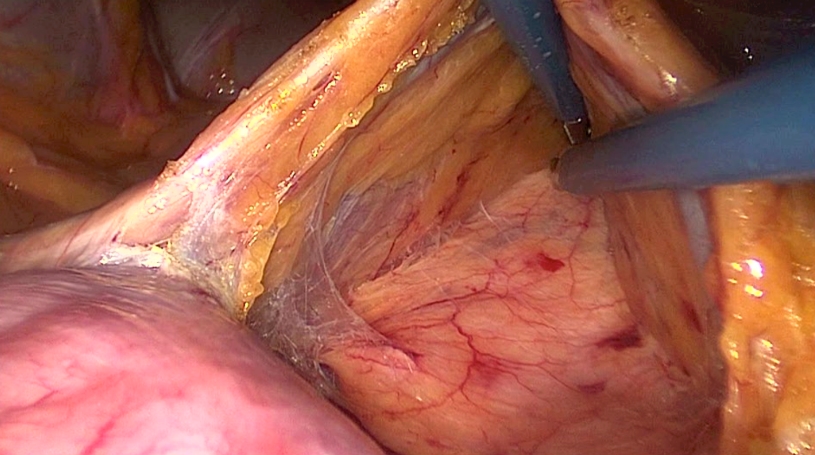

The first step is to divide the attachments to the duodenum and identify the VMI. The VMI is orientated horizontally by manipulating the 30° camera. In a line parallel to and just under the inferior mesenteric vein dissection is started from medial to lateral. By identifying Gerota’s fascia and staying in the submesocolic plane an almost bloodless dissection can be performed.

Toldt’s fascia in purple and Duodenum in pink.

(Copyright Dr. Joep Knol)

The incision is enlarged to both sides to create a nice window.

The VMI serves as a “bridge” to work under.